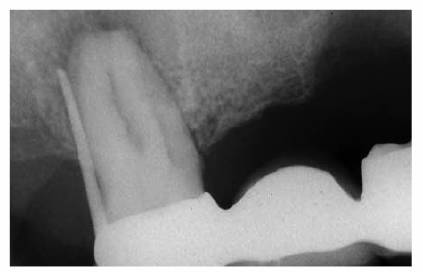

Prior to cementation, Yamada (personal communication, 2001) re-radiographs the

prepared teeth (Figures 19-25A

and B).

These images check the pulpal, periapical, and periodontal status of the teeth.

Also, the radiographs, unencumbered by the presence of the metal castings,

provide a chamber/canal road map record if the tooth requires endodontics in

the future. This may appear pessimistic, but Arens and Chivian reported that

over 40% of teeth requiring root canal therapy are crowned.4 Prior

knowledge of the size, location, and direction of the chamber and the canal will

reduce the possibility of (1) crown damage during access opening, (2) lost time

searching for the canal orifice, (3) perforations of the chamber or the canal

because of disorientation, (4) natural core elimination by gutting, (5) crown

dislodgment, and (6) sufficient destruction to alter the situation and require

corrective surgery. Each of these iatrogenic possibilities reduces the

prognosis and jeopardizes the tooth's reliability as an abutment.

Figure 19-25A and B: Precementation radiographs provide a road map to the canals if endodontic therapy is necessary after cementation of the castings. (Radiographs courtesy of Dr. Henry Yamada.)